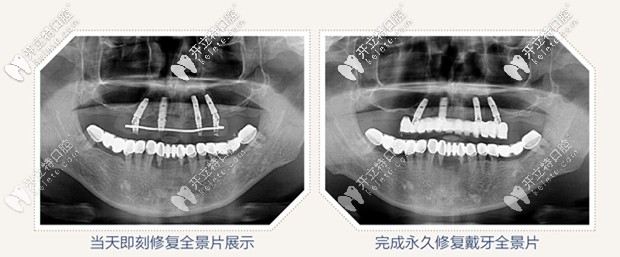

全景片圖示

all on 4即刻種植,只需要植入4顆種植體,就把老爸上半口牙就全給修復(fù)啦,并且是當(dāng)天修復(fù),當(dāng)天戴牙啊,感覺太神奇啦!

All-on-4即刻種植牙效果圖